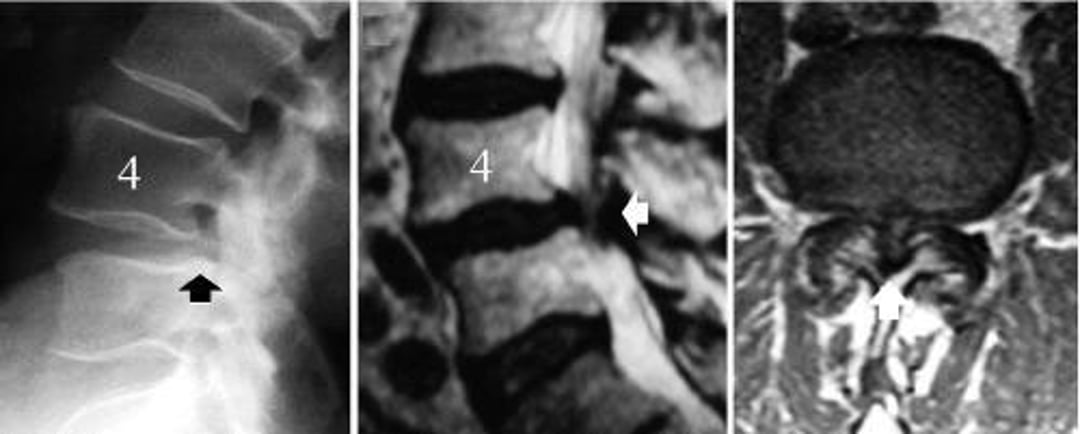

Hẹp cột sống thắt lưng gây ra bởi trượt thoái hóa cột sống L4-L5

Hình ảnh bên trái là phim chụp X-quang cột sống thắt lưng nghiêng cho thấy đốt sống L4 bị trượt (mũi tên đen – bờ sau của thân đốt sống L5 không thẳng hàng với bờ sau của đốt sống L4). Hình ảnh ở giữa là MRI mặt cắt dọc giữa cho thấy sự chèn ép các cấu trúc thần kinh (mũi tên trắng). Hình ảnh bên phải là hình ảnh chụp MRI trục cho thấy tình trạng hẹp ống sống nặng ở mức độ trượt đốt sống do thoái hóa, L4-5 (mũi tên trắng).